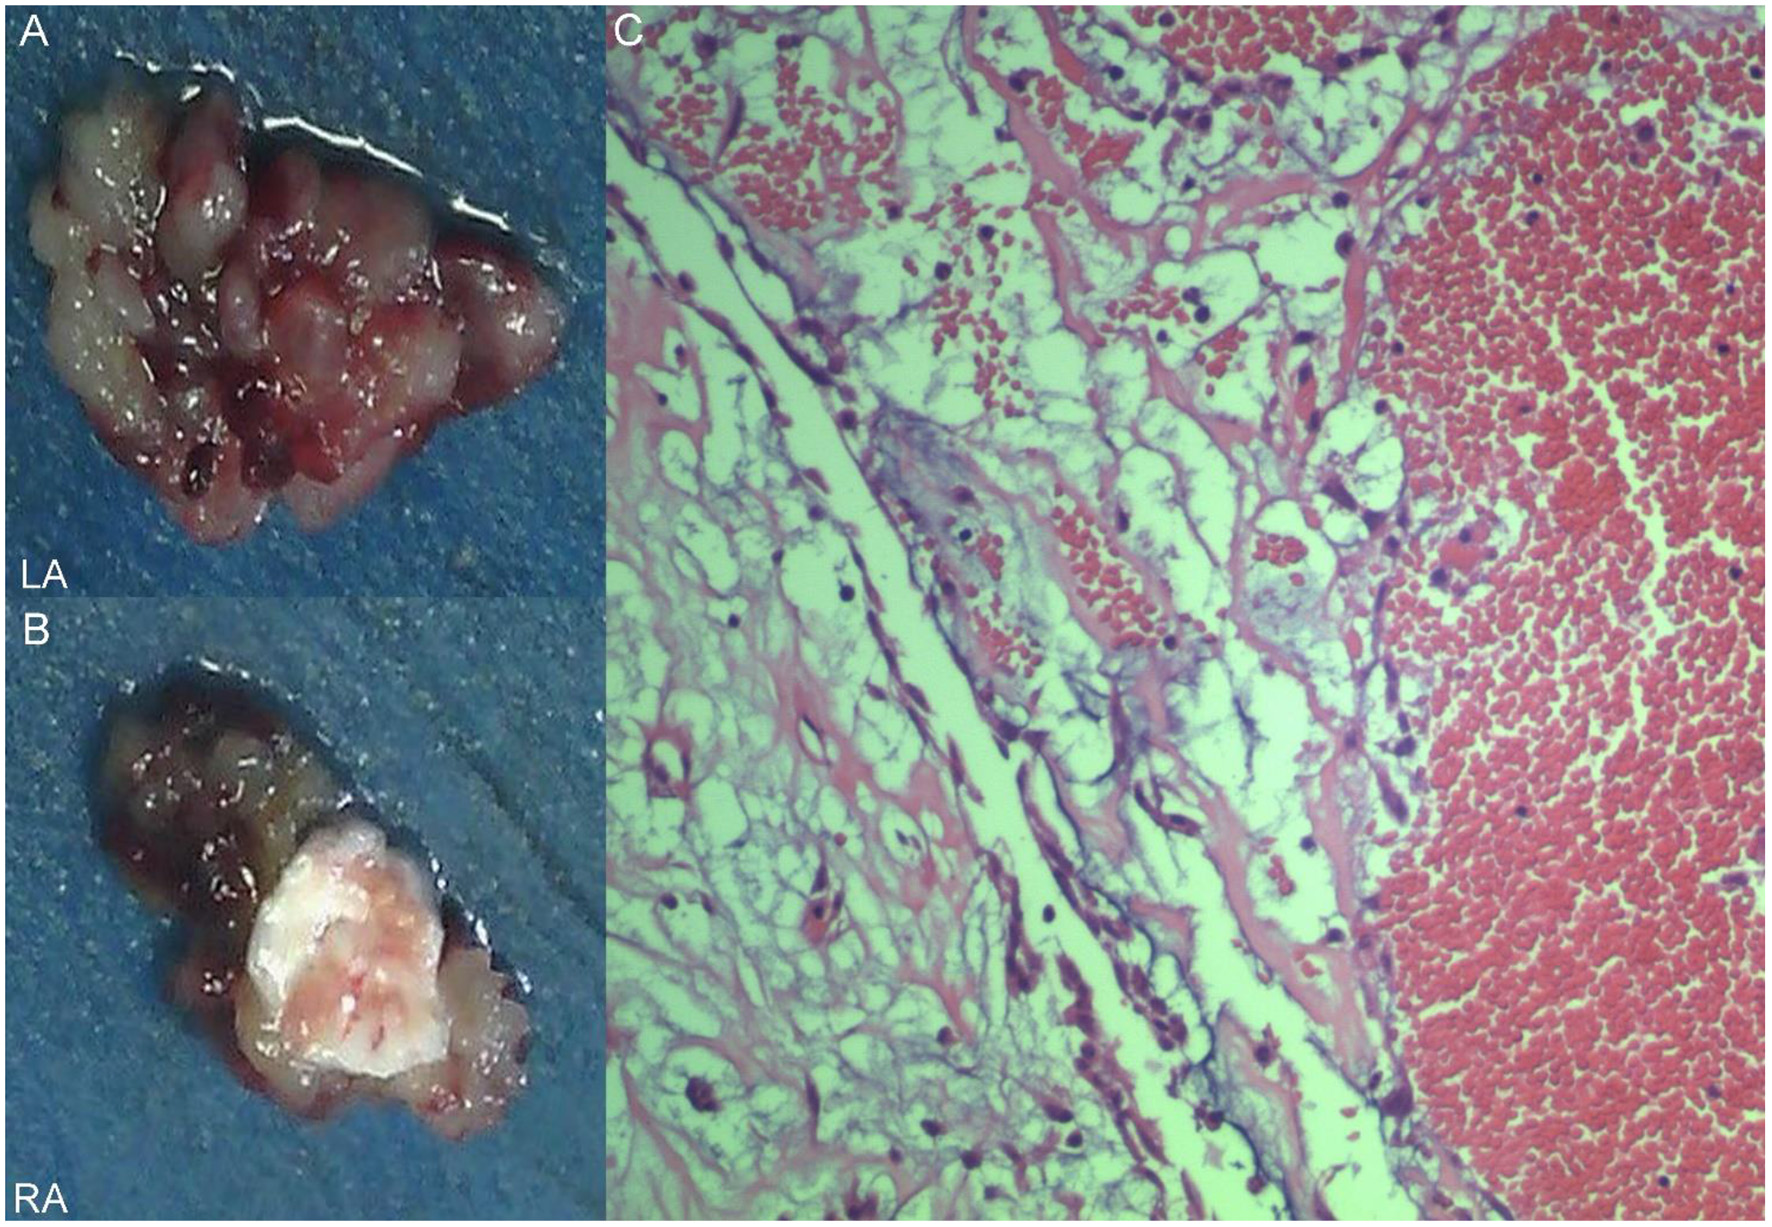

Figure 4

Excised villous biatrial atrial myxoma (A,B) and histology of atrial myxoma. Acid-mucopolysaccharide matrix with characteristic astrocytes and spindle cells which have ovoid nuclei and are surrounded by thin-walled capillaries (Hematoxylin and Eosin, × 200) (C).

A 17-year-old girl presented to our hospital on August 22, 2021 with clouding of consciousness for more than 3 days. At 3+days prior, the patient was unable to speak the patient was unable to speak when called softly and unable to open the right eye, combined with involuntary movements of the limbs and incontinence. The patient visited the local hospital immediately, where relevant tests were performed, suggesting intracranial lesions. Since the specific treatment measures were unavailable at the previous hospital, she was transferred to our hospital for further treatment. There was no history of trauma or familial genetic diseases, such as high blood pressure and diabetes. Physical examination revealed a body temperature of 37.0°C, heart rate of 110 bpm, regular heart rhythm, blood pressure of 113/77 mmHg, and no pathological murmurs in the valve region; pulmonary auscultation revealed coarse rales in the entire lung. The pupils were equal, round, and pupillary light reflexes were delayed. Both lower limbs exhibited hypertonia and hyperreflexia of the knee and tendon reflexes. Laboratory examinations revealed the following levels (normal range): coagulation function test showed D-dimer was 0.57 mg/L (< 0.5 mg/L) and fibrinogen was 5.82 g/L (2.00–4.00 g/L). Routine blood tests showed that the absolute value of neutrophils was 7.38 × 109/L (1.8 × 109/L−6.3 × 109/L). Infection-related markers showed that the hypersensitive C-reactive protein level was 111.563 mg/L (0.068–8.200 mg/L). Creatine kinase, α-hydroxybutyrate dehydrogenase, and lactate dehydrogenase levels were 148 U/L (26–140 U/L), 218 U/L (90–180 U/L), and 295 U/L (140–271 U/L), respectively. Computed tomography pulmonary angiography (CTPA) detected filling defects in the right atrium, left atrium, and left lower pulmonary basilar artery (Figure 1), and a diagnosis of Pulmonary embolism was made. Transthoracic echocardiography (TTE) revealed irregular iso-echoic masses in the bilateral atrium that were likely myxomas, given their location and appearance in a young patient; the myxoma in the left atrium measured approximately 38 × 21 mm, and it was attached to the junction of the lower part of the interatrial septum (IAS) and the root of the anterior mitral leaflet; in the right atrium it measured approximately 51 × 27 mm, and it was attached to the lower part of the IAS (Figure 2A). These masses resulted in the acceleration of the tricuspid valve antegrade flow (Figure 2B). Craniocerebral computed tomography (CT) showed extensive hypodensity in the bilateral parts of the pons and patchy hypodensity in the left corona radiata area and bilateral basal ganglia areas. Magnetic resonance imaging (MRI) also revealed extensive hypointensity on T1-weighted imaging and hyperintensity on T2-weighted imaging in the bilateral parts of the pons, and a patchy hyperintensity on T2-weighted imaging in the bilateral basal ganglia areas; bilateral centrum semiovale; and right frontoparietal lobe, which presented as high signal on diffusion-weighted imaging (DWI) (Figure 3). This confirmed the diagnosis of brain ischemia. To prevent thrombosis, low molecular weight heparin calcium (subcutaneous injection, 0.4 ml/12 h) was commenced on the second day of admission and continued until discharge. The patient underwent successful removal surgery for a biatrial myxoma. The masses were sent for histological examination, which confirmed the presence of a myxomatous matrix containing myxoma cells (Figure 4). The patient recovered uneventfully and was discharged 9 days after the procedure. The patient has been followed-up postoperatively for over 2.5 months, and limb motor function of the patient has recovered to some degree, but there is intellectual and cognitive decline.